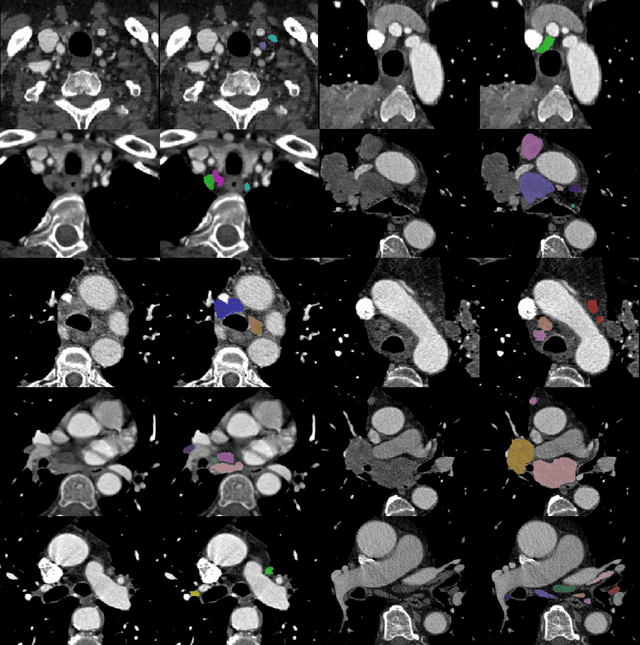

Abstract:As lung cancer evolves, the presence of enlarged and potentially malignant lymph nodes must be assessed to properly estimate disease progression and select the best treatment strategy. Following the clinical guidelines, estimation of short-axis diameter and mediastinum station are paramount for correct diagnosis. A method for accurate and automatic segmentation is hence decisive for quantitatively describing lymph nodes. In this study, the use of 3D convolutional neural networks, either through slab-wise schemes or the leveraging of downsampled entire volumes, is investigated. Furthermore, the potential impact from simple ensemble strategies is considered. As lymph nodes have similar attenuation values to nearby anatomical structures, we suggest using the knowledge of other organs as prior information to guide the segmentation task. To assess the segmentation and instance detection performances, a 5-fold cross-validation strategy was followed over a dataset of 120 contrast-enhanced CT volumes. For the 1178 lymph nodes with a short-axis diameter $\geq10$ mm, our best performing approach reached a patient-wise recall of 92%, a false positive per patient ratio of 5, and a segmentation overlap of 80.5%. The method performs similarly well across all stations. Fusing a slab-wise and a full volume approach within an ensemble scheme generated the best performances. The anatomical priors guiding strategy is promising, yet a larger set than four organs appears needed to generate an optimal benefit. A larger dataset is also mandatory, given the wide range of expressions a lymph node can exhibit (i.e., shape, location, and attenuation), and contrast uptake variations.